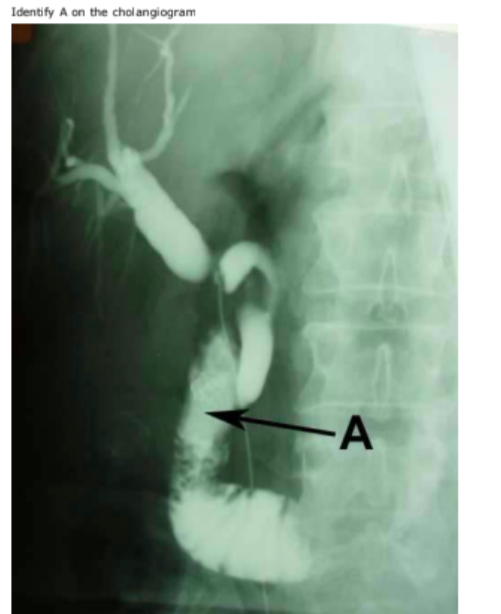

Q

in this cholangiogram the radioopaque dye has entered the duodenum (A is pointing to the 2nd part). The plicae circulares can be seen.